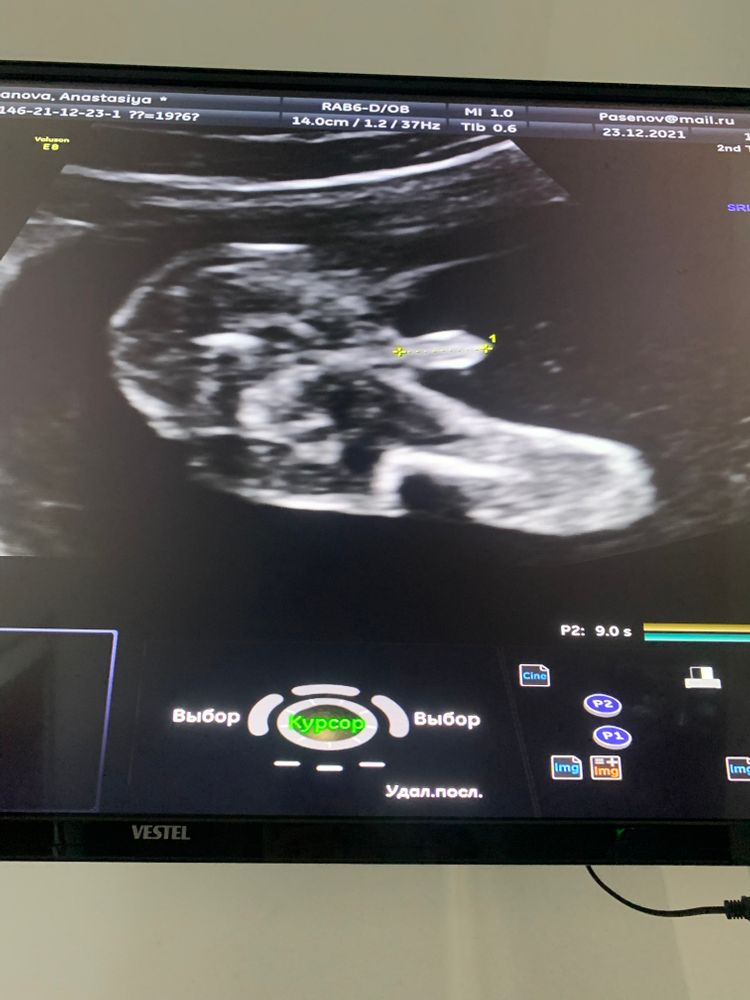

О ну вот это уже вполне хороший снимок, и прогадать тут не возможно!) вот наш 😄, вид снизу, даже выделили 🌶 Изображение

20.01.2022

Karmilla, у вас точно не ошибёшься! 😆